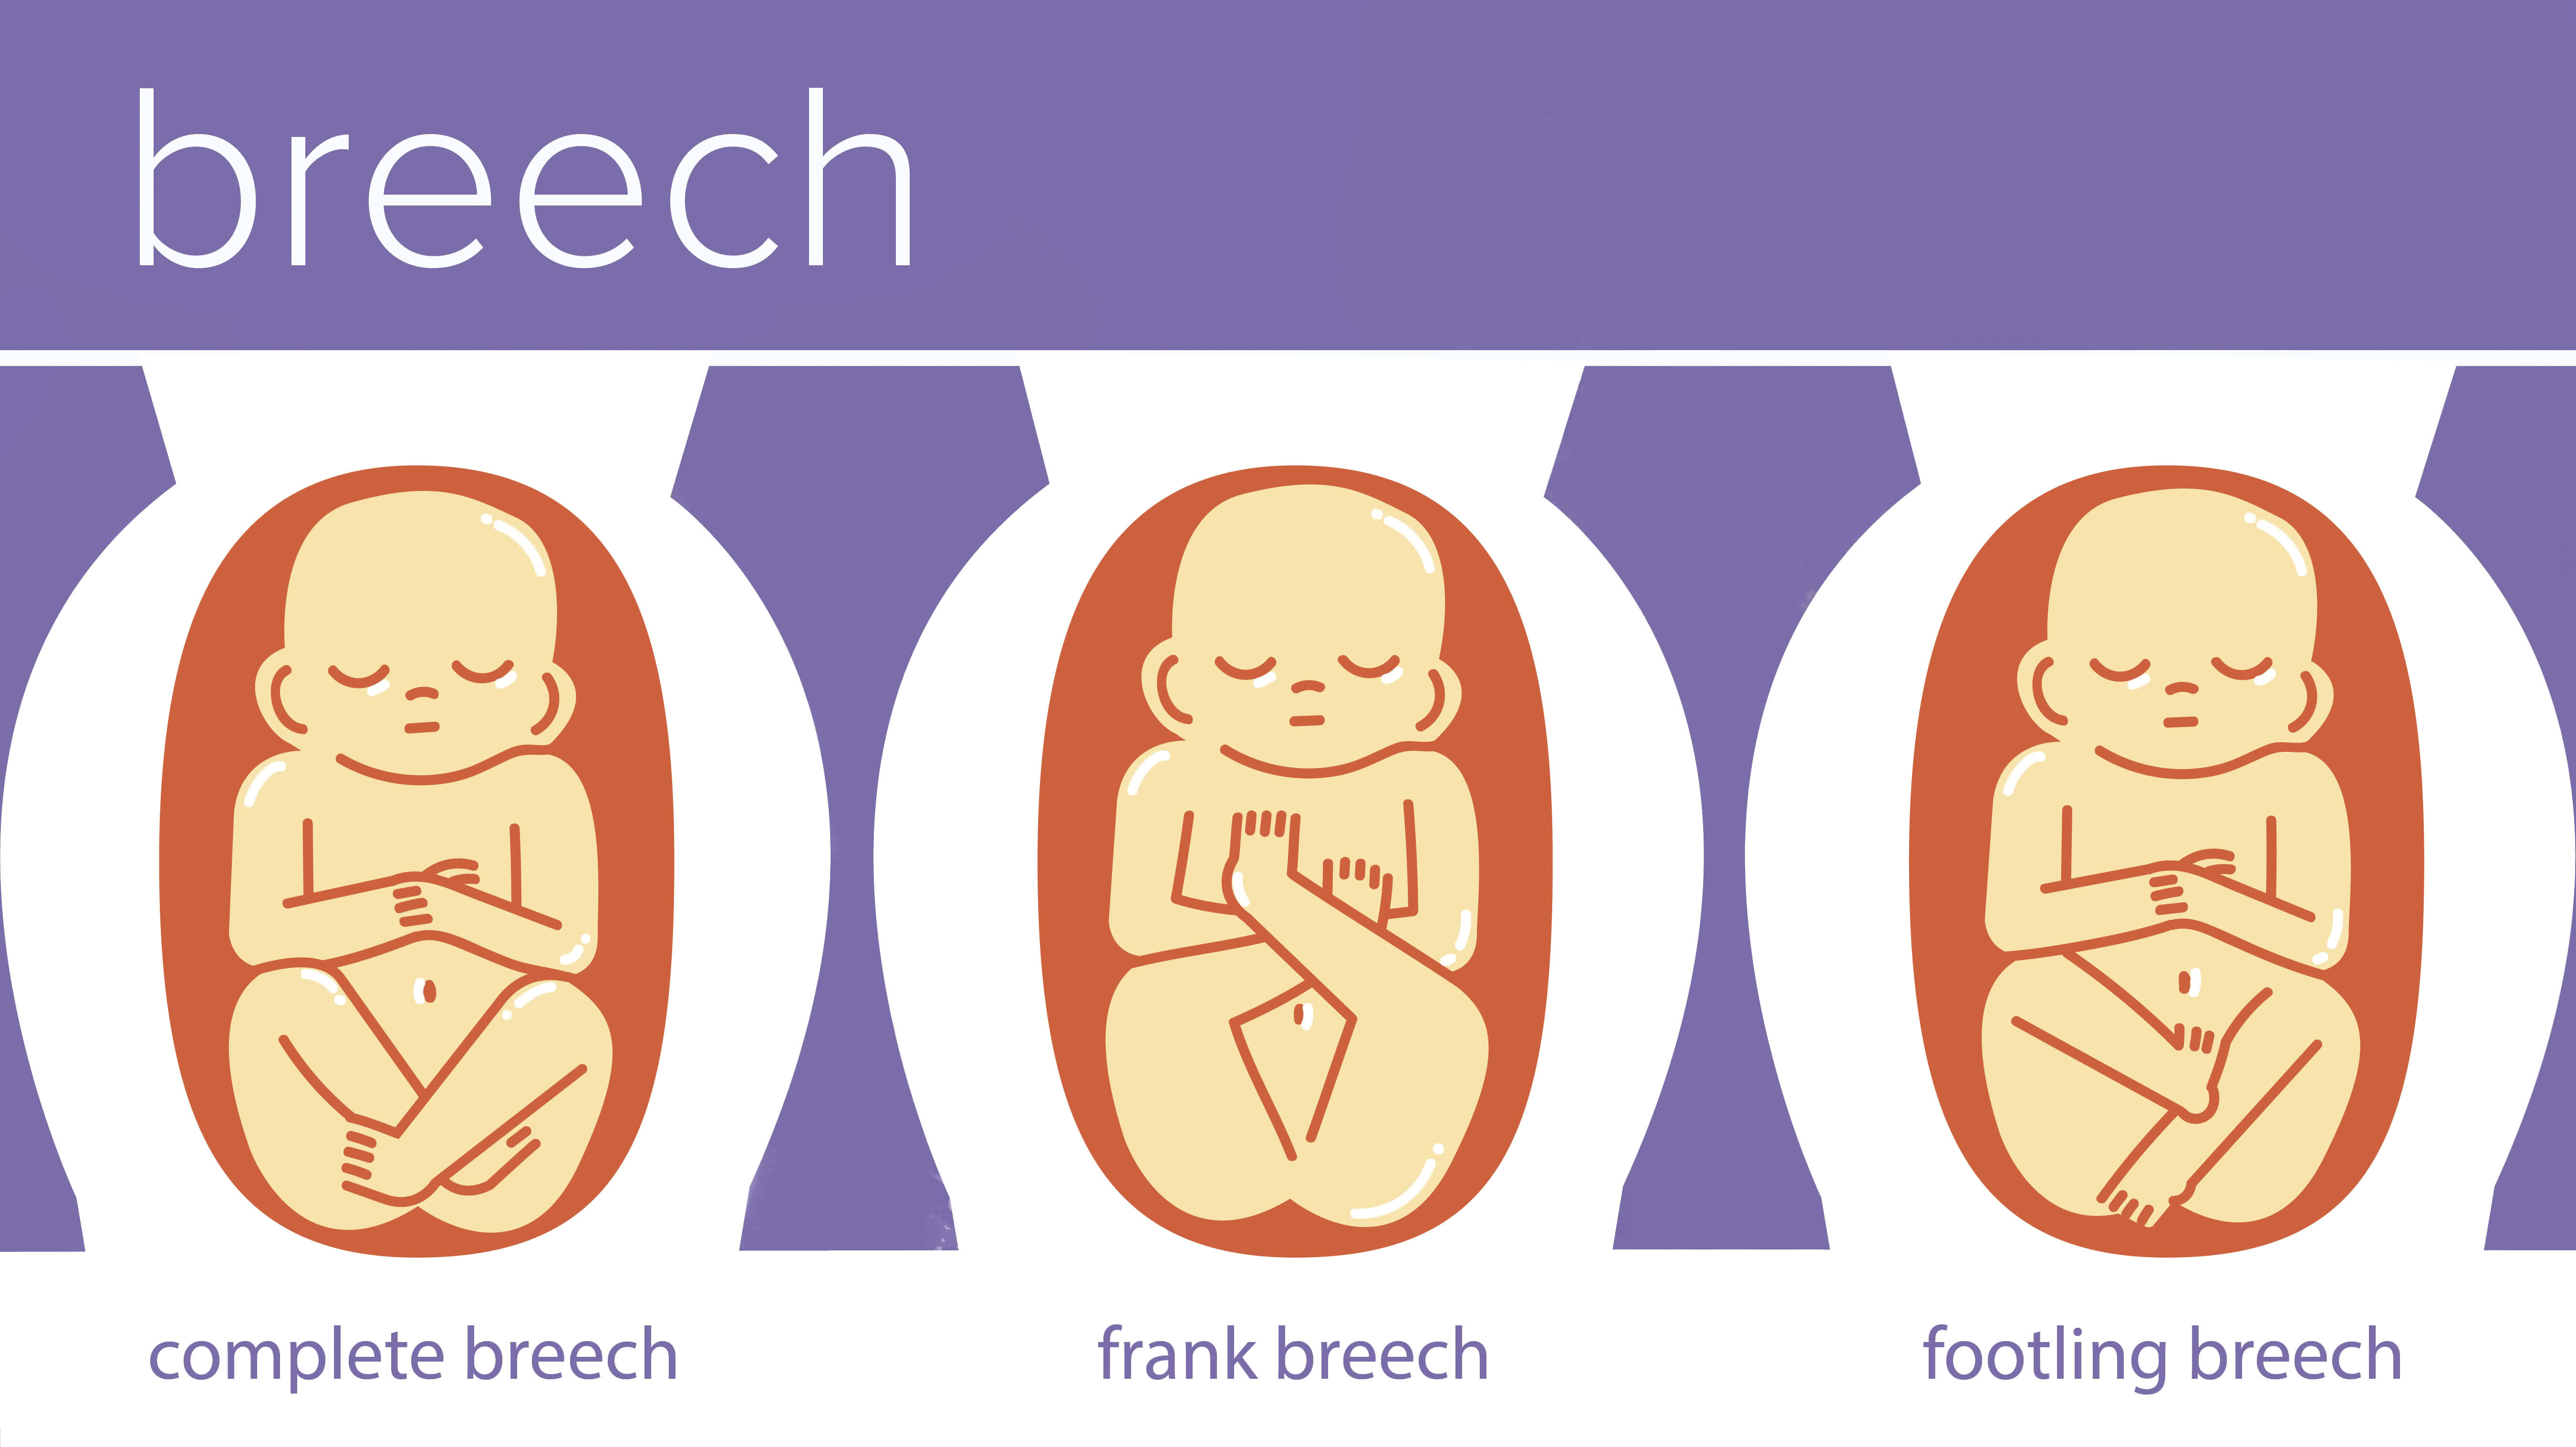

Во время беременности, положение плода имеет большое значение для мамы и малыша. Одним из типичных положений является продольное предлежание головное. В этом положении голова малыша находится внизу, а ножки - наверху. Это положение достаточно распространено и предпочтительно для естественных родов.

Breech.webp)

Живот с ягодичным предлежанием